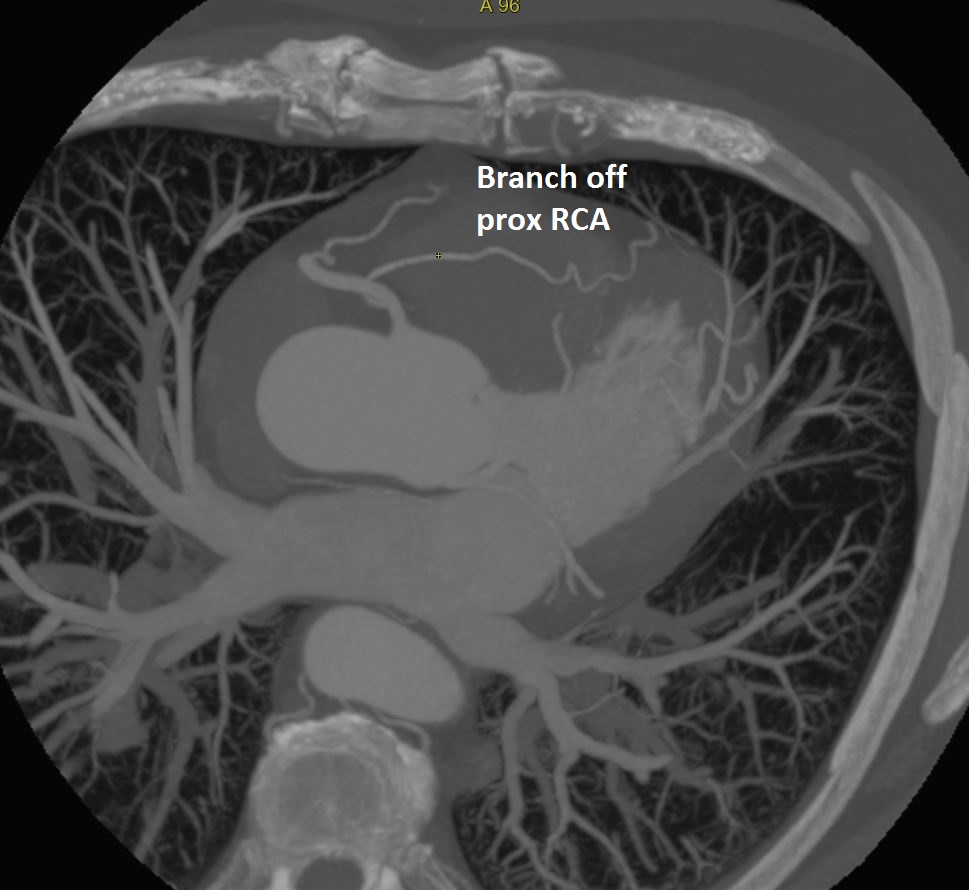

Nice case of #YesCCT RCA to coronary sinus (CS) fistula (red arrow) with giant tortuous RCA @Heart_SCCT @AChoiHeart @mmartinezheart @CardiacConsult @lillian_aldaia @LindaGillamMD